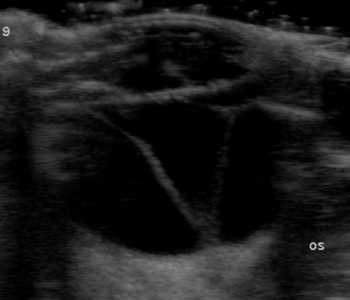

【超音波(エコー)検査】

目の中、特に硝子体や網膜など水晶体の裏側がどのような状態なのか調べます。エコー検査により、白内障の混濁状態や網膜剥離や眼内出血などの合併症の評価を行います。

犬 網膜剥離

網膜剥離